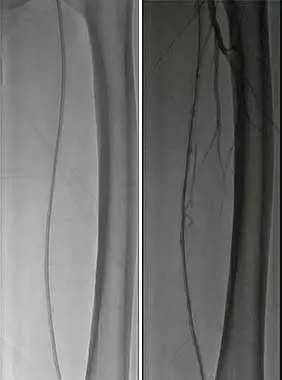

4、減容后,以SABER3mm*30cm球囊預擴張。

5、使用Matrix Super PTX (巴泰醫療)5mm*20cm及5mm*15cm約束型藥物涂層球囊全程擴張左股淺動脈病變。

6、復查造影見:左股淺動脈血流通暢,殘余狹窄小于 30%,左下肢血供明顯改善,撤出鞘管,封合器封合右股動脈穿刺點,安返病房。